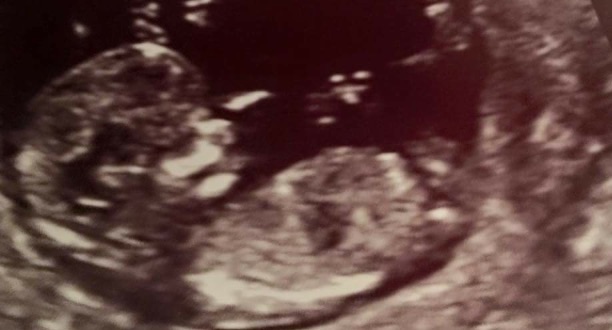

Has she got any other pics? I'm not sure if that is a girl nub or if there is some slight stacking there (boy).

No other pics unfortunately..thanks anyway! I think the skull looks boyish though..

boy lean